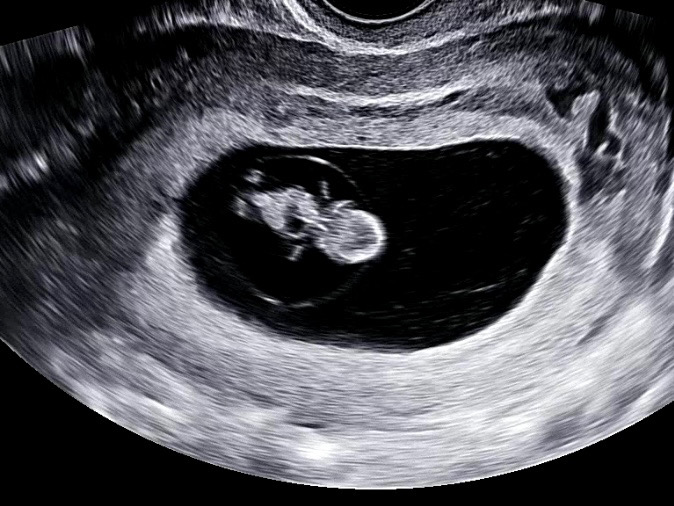

8주 4일차 계류 유산

오늘 8주 4주차에 병원을 갔는데 태아 심장이 뛰지 않는다고… 주수 크기로는 지금 들어맞아서 어제 아니면 오늘 심정지 된거 같다고 하네요 ㅠㅠ 너무 속상 퓨ㅠㅠㅠㅠ 담주 월요일 소파술 하기로 했습니다